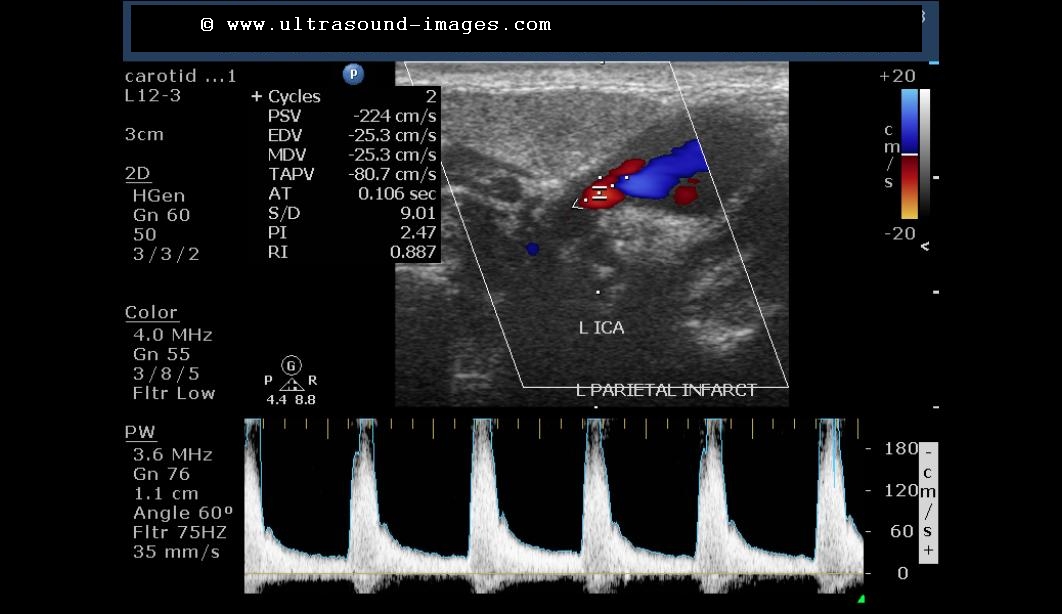

This patient has the right hemiplegia following a cerebrovascular accident involving the left parietal lobe. Color Doppler imaging of the carotid tree shows severe stenosis, 80 to 90%, involving the left internal carotid artery close to its origin from the common carotid artery.

The colour Doppler image below shows the internal diameter of the left internal carotid artery is less than 3 mm near its origin. This is definitely abnormal and shows severe stenosis.

however, the left internal carotid artery shows a definite evidence of severe stenosis with peak systolic velocity reaching up to 224 cm/s suggesting greater than 90% stenosis at this level. The normal peak velocity of flow at the internal carotid artery should be less than an and 120 cm/s.